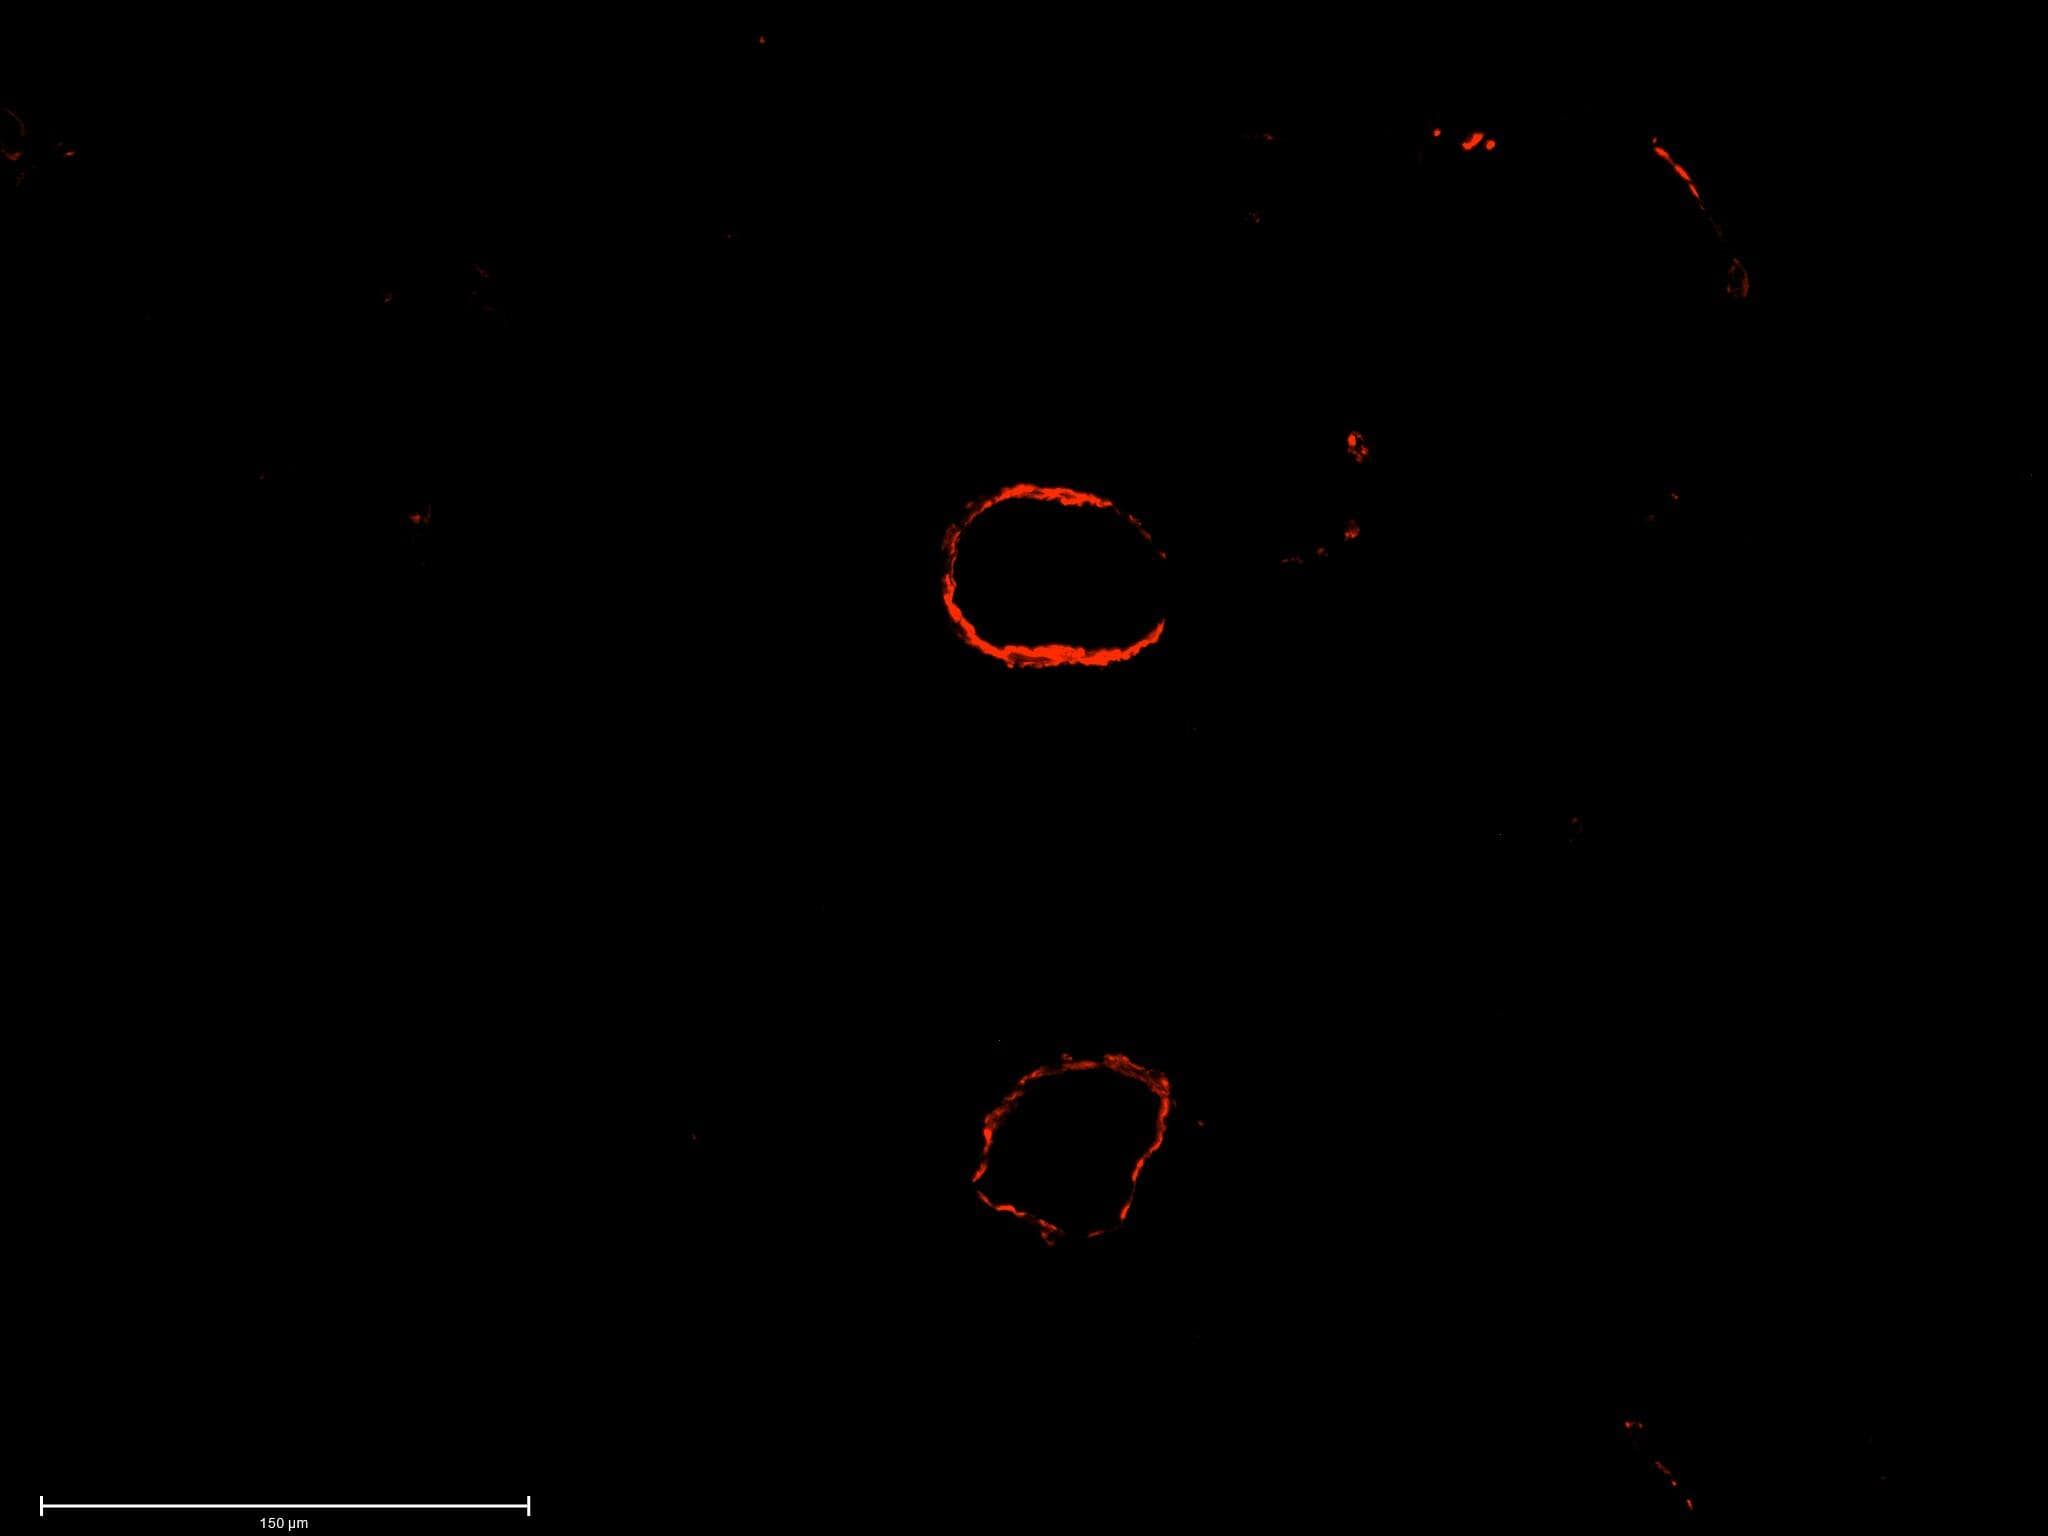

Multiplex Immunofluorescence

0.5 µg/mL

Sample: Immersion fixed paraffin-embedded sections of human breast cancer, prostate tumor, colon tumor and normal kidney tissue